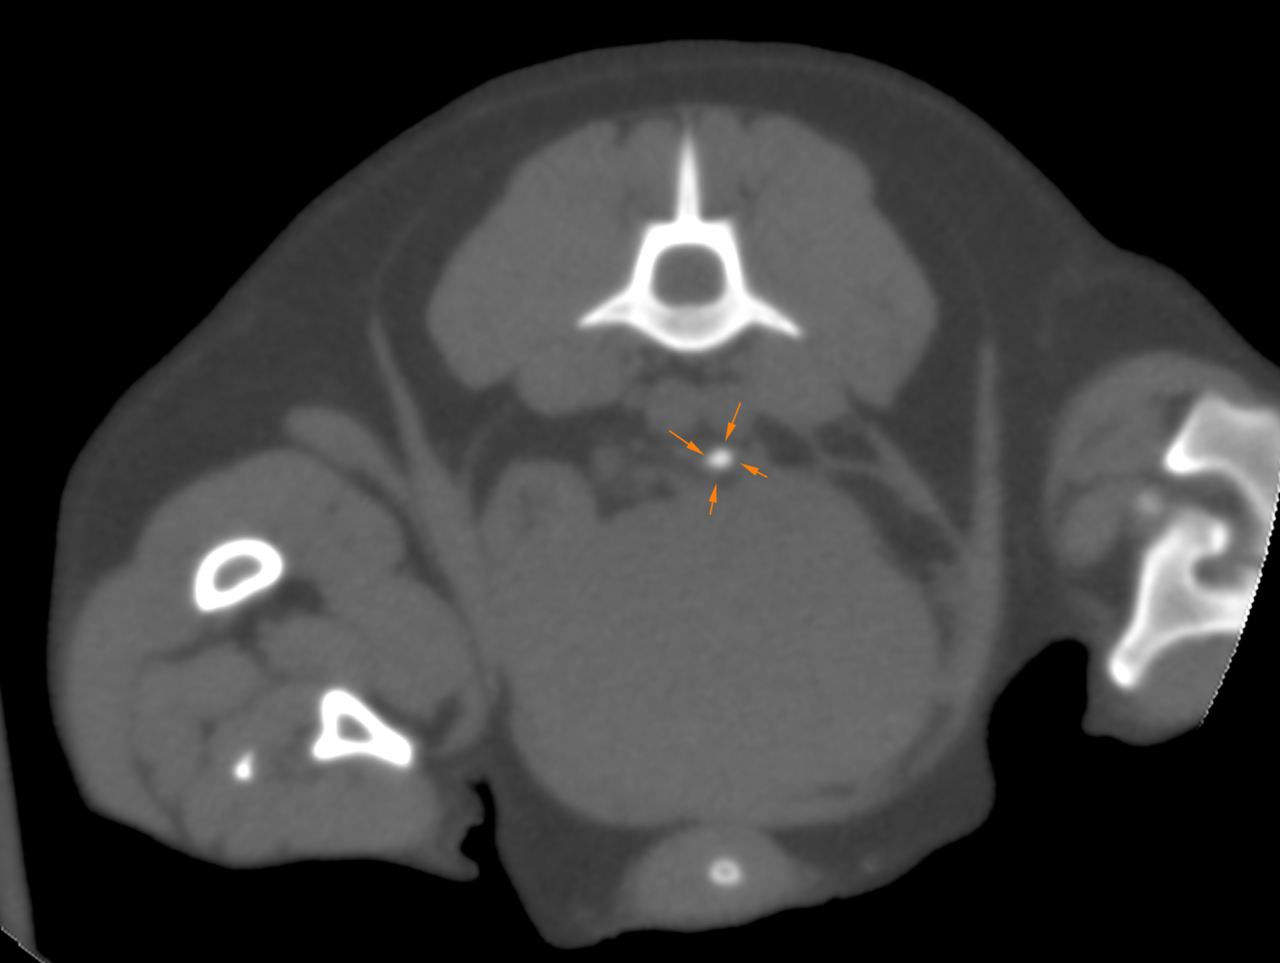

パピヨンの尿管結石症例に対し、外科的に結石摘出を実施した。摘出結石の分析により、成分はシリカ(ケイ酸、SiO₂)と同定された。シリカ結石は犬の尿石症の中でも発生頻度が極めて低いとされ、特に上部尿路(尿管)での発生報告は限られている。また、本結石は溶解療法が無効であり、尿管閉塞を伴う症例では外科的摘出、尿管ステント、SUBシステムなどの介入が必要となる。本症例ではCTやエコーなどの画像診断により尿管閉塞を確認し、腎機能温存を目的として外科的摘出を選択した。術後経過は良好で、現在は再発予防として飲水管理(低ミネラル水)および食事内容の調整を中心に経過観察を行っている。シリカ結石は飲水中の溶存ケイ酸量や生活環境との関連が示唆されており、まれな結石であり、成分分析に基づく原因評価と長期管理戦略が重要であると考えられた。